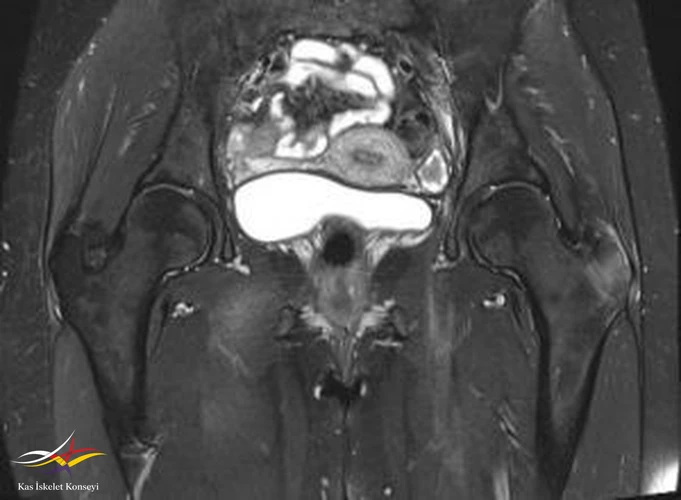

İncelemeler: Kalça MRG ve BT incelemelerinde sol femur trokanter major bölgesinde kemik iliği ödemi, bilateral şüpheli trokanterik bölge fraktür hattı, trokanterik bursit ile uyumlu görünüm saptandı.

Resim 2. Koronal T1 ağırlıklı MRG incelemesi.